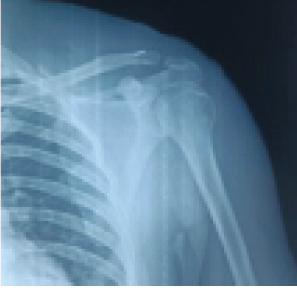

Clinical and Radiological Outcome Assessment following Coracoclavicular Reconstruction with Endobutton and Fibertape for Neer’s Type II Lateral End Clavicle Fracture: A Prospective Study.

Nikhil Baran Dash , Suraj Kumar Jain , Tushar Ranjan Dalei , Pritam Kumar Panda , Braja Sundar Sahoo